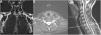

We conducted basic and needle-EMG examinations and found a severe inferior brachial plexopathy associated with severe chronic neurogenic impairment in the C8 and T1 innervated muscles. Further examination with magnetic resonance imaging (MRI) excluded any discoradicular conflict at the level of C8 and T1 but identified small excess of fat and edema in the form of a “teardrop” surrounding C8 and T1 suggesting compression of these nerves at the thoracic outlet level (Fig. 2). A standard radiography of the cervical spine clearly showed an abnormally elongated left C7 transverse process (Fig. 3). A diagnosis of TN-TOS was concluded.

Coronal (A), axial (B) and sagittal (C) MRI of the cervical spine. The coronal recordings are Dixon sequences where fat is emphasized (A), the axial and sagittal recordings are Dixon sequences where water is emphasized (B, C). (A) Notice more fat in the form of a “teardrop” (white on this image) around the left C8 under the transverse process (arrows), compared to right. (B, C) Hyperintensity around left nerve C8 (arrow), indicating more edema than on the right.